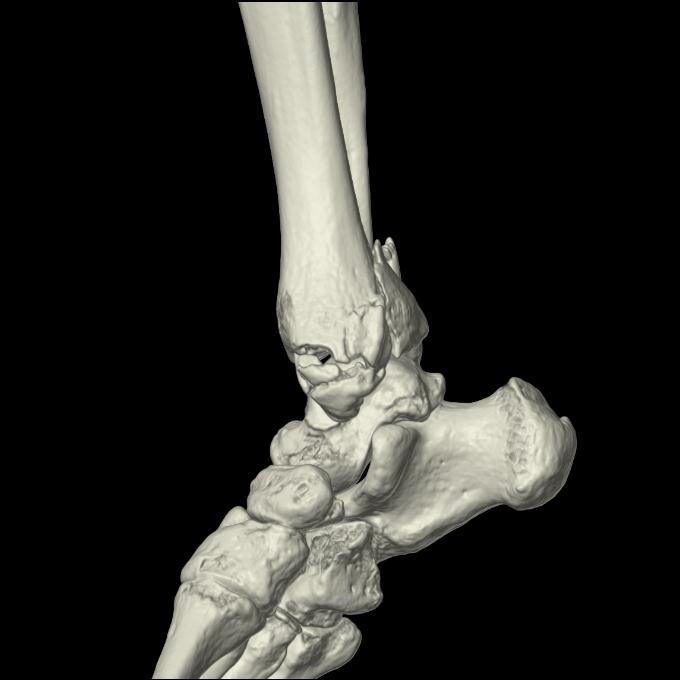

102755 1/4 2R 1/15 2R 右足関節 68歳女性 右三果脱臼骨折